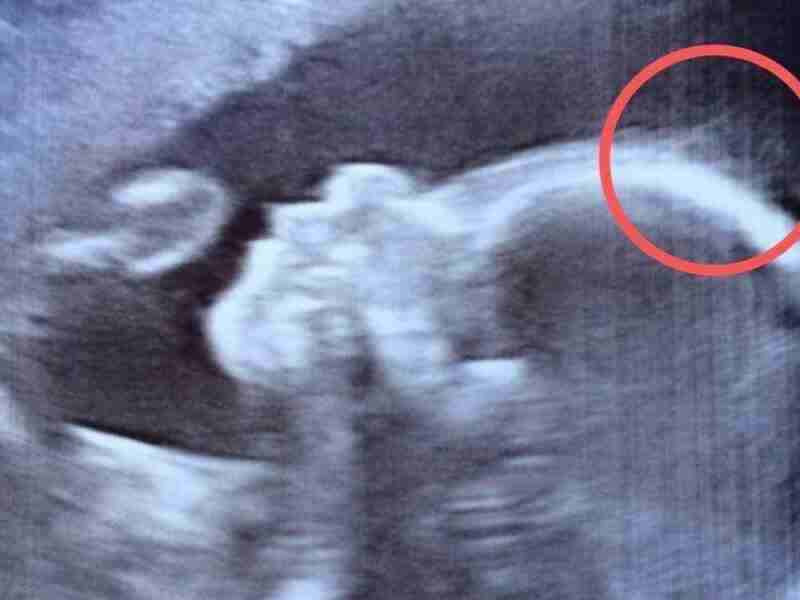

Ahora puedes leer el artículo de UpSocl sobre Mujer va a un ultrasonido para ver a su bebé. Lo que nota en su cabeza, se confirma cuando nace.

Hace algún tiempo informamos de la historia de un bebé que tenía tanto cabello, como el de un adulto, a pesar que tenía solo 4 meses de vida. Hoy, medios ingleses cuentan la historia de una niña que nació con una tremenda cabellera, tanto, que era visible desde el ultrasonido del…